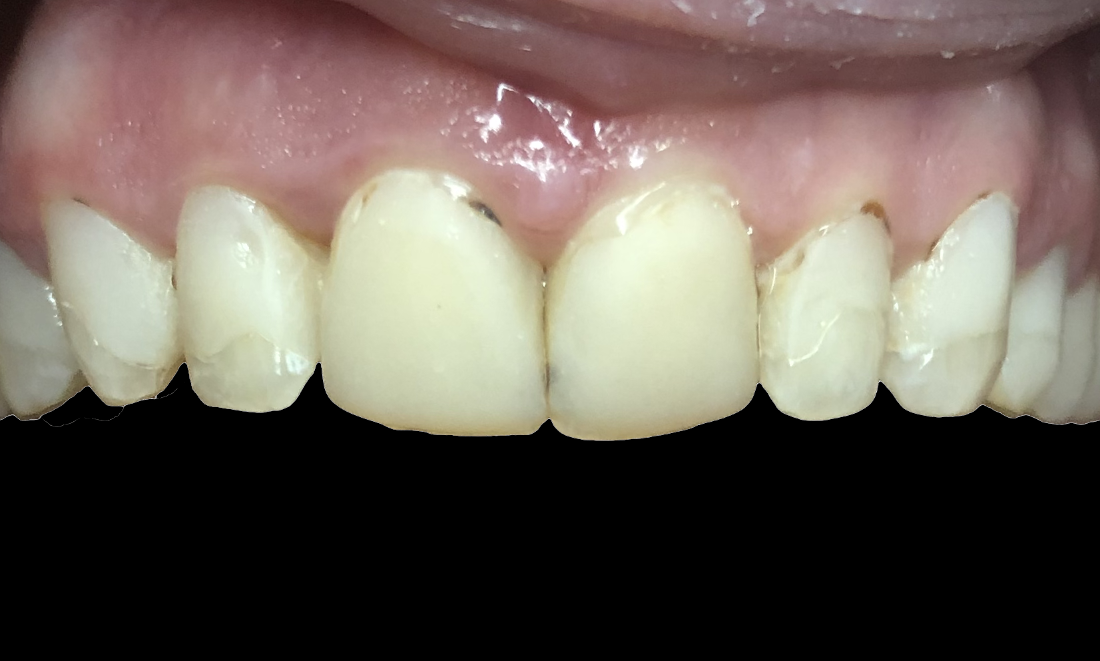

Smile Makeover

This patient suffered from cavities on her front teeth that affected her smile for years.  We placed ceramic crowns to restore her beautiful smile.